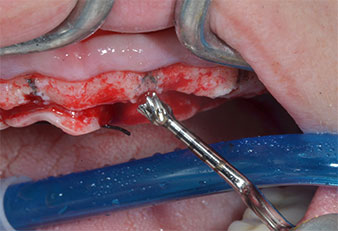

A flame-shaped, diamond-coated piezoelectric instrument (Piezomed I1) was used to mark the implant positions and to perform pilot preparation (Fig. 3). Care was taken to use an up and down movement, with reduced power, full irrigation and low pressure (below 300 g). Next a pilot instrument (Piezomed I2A/I2P) was applied for the initial 2 mm diameter enlargement of the implant sites (Fig. 4), followed by a 3 mm insert (Fig. 5).